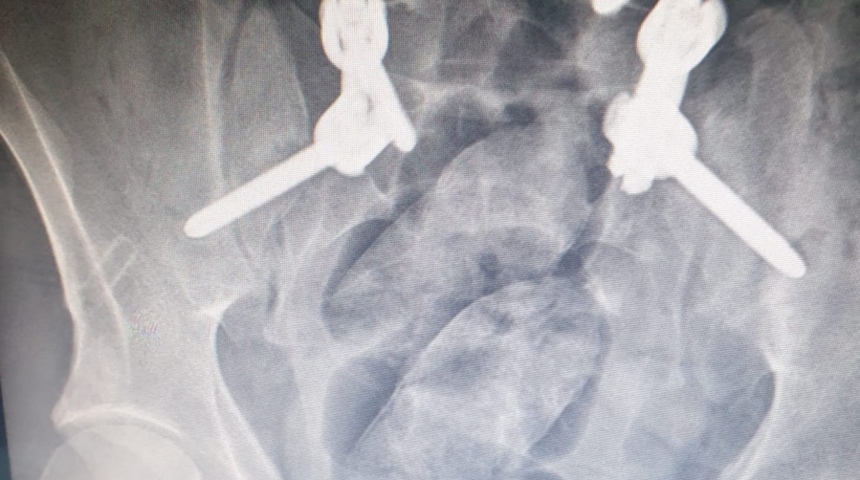

Ağrı Emniyet Müdürlüğü Narkotik Suçlarla Mücadele Şube Müdürlüğü ekipleri, 17 Kasım'da, İran'dan Türkiye'ye giriş yaptığını belirledikleri F.A.'yı Doğubayazıt'ta takibe aldı. Hasankeyf Mahallesi Çevreyolu Bulvarı'nda gözaltına alınan ve Dr. Yaşar Eryılmaz Devlet Hastanesi'nde muayene edilerek röntgen filmi çekilen şüphelinin midesinde, yabancı cisimler tespit edildi.

F.A.'ya ilaç verilerek, midesindeki cisimlerin doğal yollarla çıkarılması sağlandı. Yapılan incelemede çıkan cisimlerin; 3 paket halinde 124,9 gram metamfetamin, 4,65 gram reçine esrar olduğu belirlendi. F.A., 'uyuşturucu veya uyarıcı madde ticareti yapma veya sağlama' suçundan sevk edildiği adliyede çıkarıldığı hakimlikçe tutuklandı.